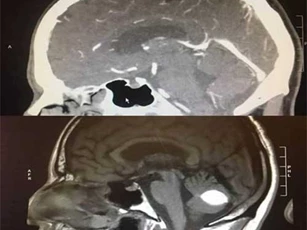

Thấy choáng, chóng mặt, nhức đầu, người phụ nữ đi khám mới biết mình có một khối u màng não. Các bác sỹ sau đó đã tiến hành hội chẩn và quyết định phẫu thuật cắt bỏ khối u.

Phim chụp CT trước ca phẫu thuật cho thấy khối u não đã biến mất một cách kỳ lạ mà không ai lý giải được.